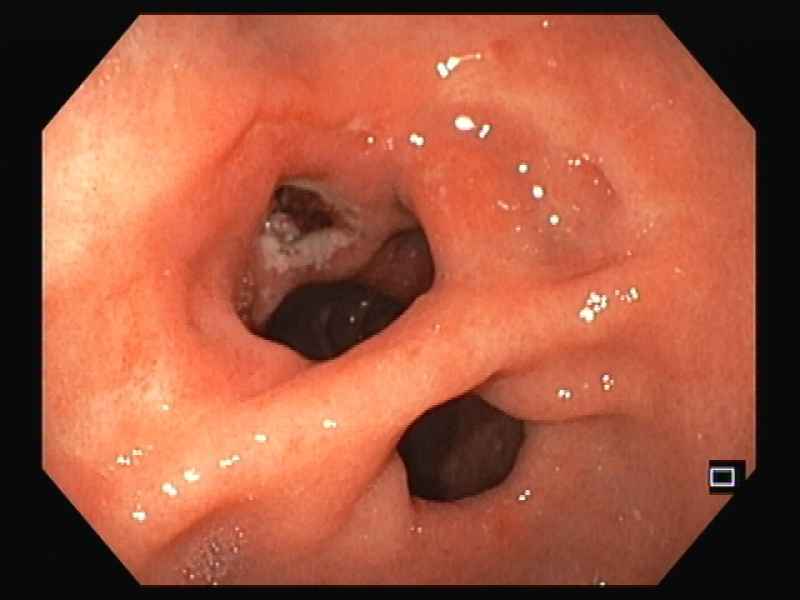

Gallstone ileus: A rare cause of bowel obstruction in a liver transplant patient

Fotografia